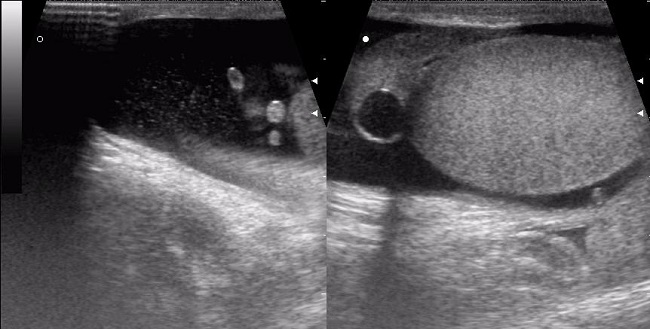

Для подтверждения диагноза применяются диафаноскопия и эхография. Диафаноскопия включает в себя освещение мошонки специальным фонарем, что позволяет определить местоположение новообразования. Эхография служит подготовительным этапом перед операцией, помогая установить точное место для разреза. Лабораторные исследования в случае перекрута гидатиды не имеют практического значения.